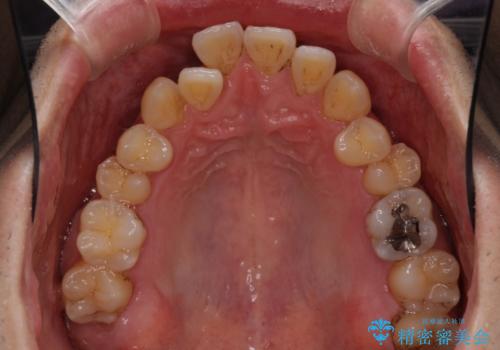

- 上下の前歯の反対咬合を気にして来院された患者様です。

インビザラインを用い、下顎はIPR(歯と歯の間を削る)と歯列全体を後方に移動させ、上顎は前歯を持ち上げることで、反対咬合を改善していくこととしました。

八重歯の歯根が見えている点も気になっているので、矯正歯科治療後に歯肉移植による根面被覆を行うこととしました。

矯正治療により元々気になっていた八重歯と、反対咬合が改善された歯の2本に対して根面被覆を行い、審美面の改善も達成しました。